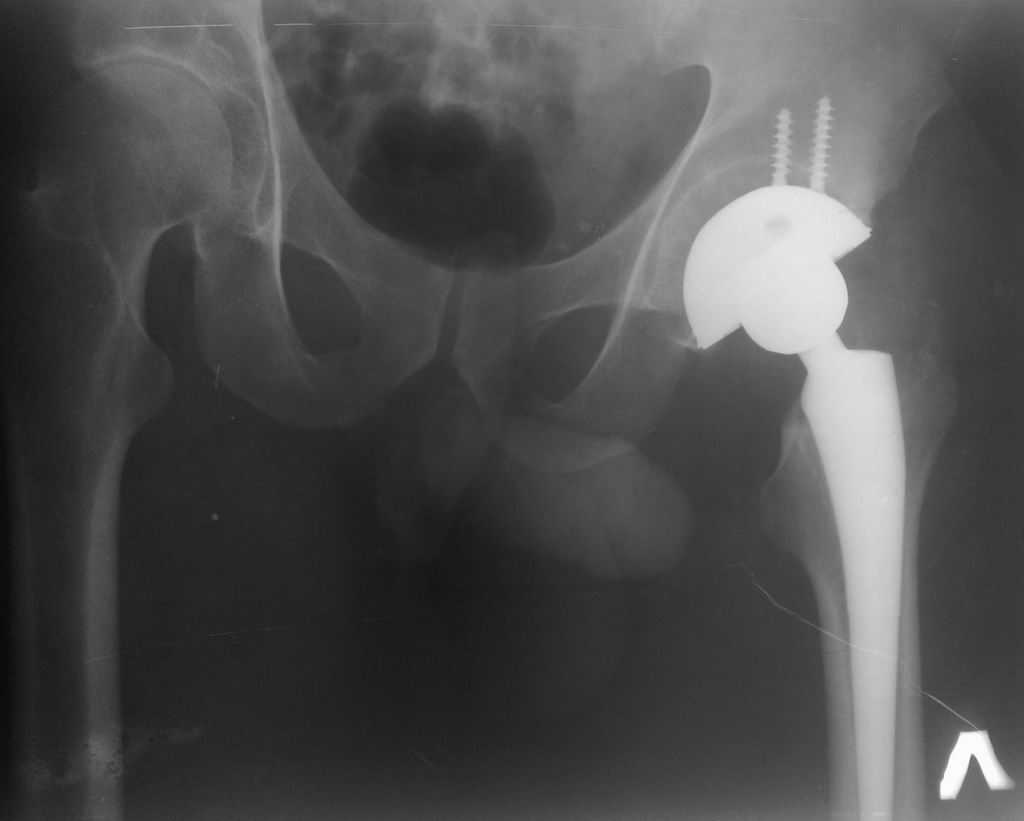

Уважаемые коллеги! Прошу вашей помощи в следующей ситуации. Больному 52 года. 18 мая

установлен эндопротез. Бесцементная чашка Varioloc от AAP Implantate AG. Чашка

"недогружена". Не буду обсуждать причины, но факт налицо. Прошу высказать мнение по тактике

ведения. В отделении мнения разделились: часть коллег считает, что необходима ревизия с

переустановкой чашки и заменой вкладыша. Аргументы - чашка держится только на краях и 2

винтах. Ждать здесь нечего - вся эта конструкция в скором времени расшатается и сломаются

винты. Другие предлагают выжидательную тактику, мотивируя опасностью нагноения после

повторной операции: когда возникнет нестабильность: тогда и будем делать ревизию.